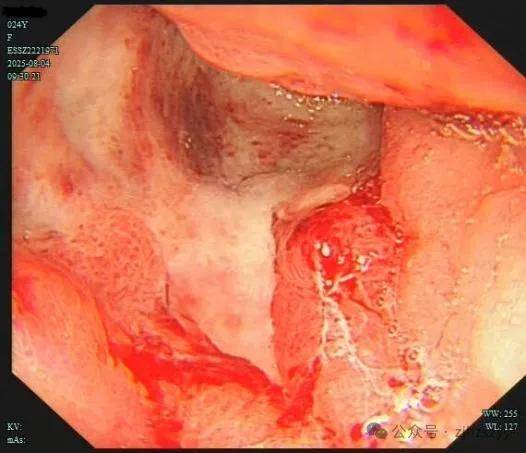

直到她开始频繁出现黑便,并在片场拍戏时几次呕血,才被同事紧急送往我院急诊。情况紧急,医生立即为小雯安排了急诊胃镜检查,发现她整个胃窦被一巨大的溃疡占据,黏膜组织变得僵硬、缺乏弹性,好似“皮革”一般。而随后的活检结果,更是给了这个年轻姑娘沉重一击——胃印戒细胞癌。